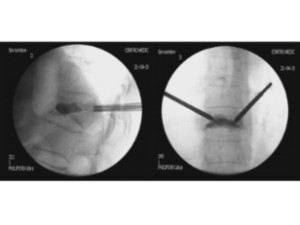

Estabilització percutània de fractures vertebrals inestables

En casos de fractures vertebrals complexes, inestables, comminutes, etc. es requereix una estabilització addicional de la fractura mitjançant una artròdesi percutània, i en alguns casos en els quals hi ha compromís neurològic, una descompressió del canal medul·lar. L’artrodesi percutània permet estabilitzar l’estructura compromesa de la columna vertebral i descarregar la càrrega del pacient sobre la fractura. Addicionalment se solen cementar les vertebres artròdesis i la fractura vertebral mitjançant cifoplastia.

Fractura Vertebral Ejemplo de Caso Clínico